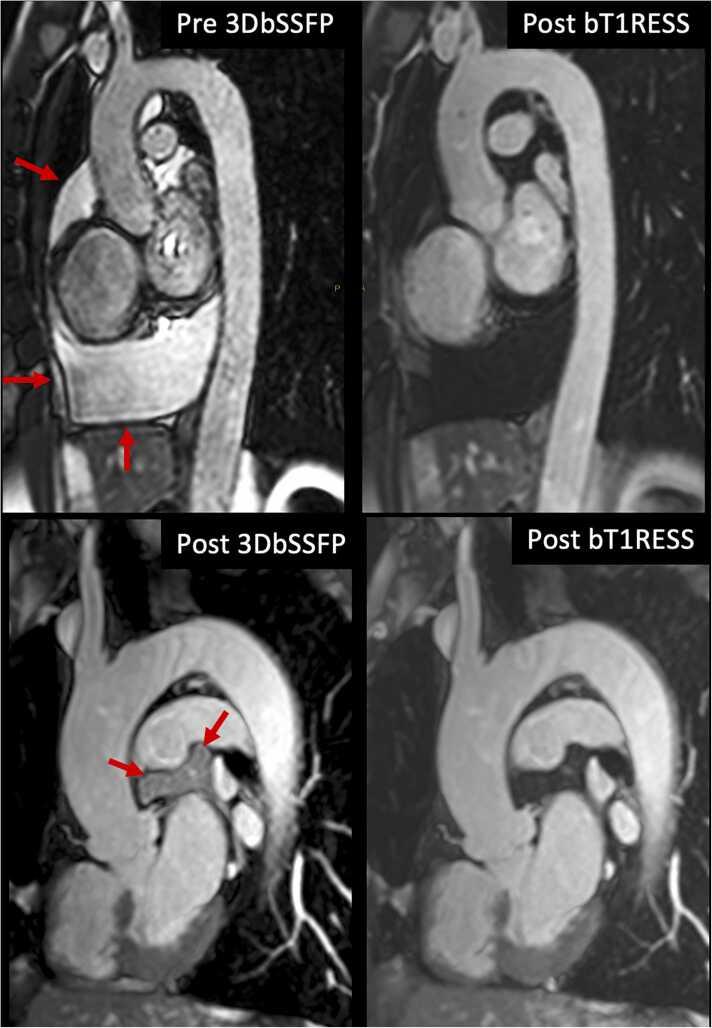

Three-dimensional (3D) contrast-enhanced magnetic resonance angiography (CEMRA) is routinely used for vascular evaluation. With existing techniques for CEMRA, diagnostic image quality is only obtained during the first pass of the contrast agent or shortly thereafter, whereas angiographic quality tends to be poor when imaging is delayed to the equilibrium phase. We hypothesized that prolonged blood pool contrast enhancement could be obtained by imaging with a balanced T1 relaxation-enhanced steady-state (bT1RESS) pulse sequence, which combines 3D balanced steady-state free precession (bSSFP) with a saturation recovery magnetization preparation to impart T1 weighting and suppress background tissues. An electrocardiographic-gated, two-dimensional-accelerated version with isotropic 1.1-mm spatial resolution was evaluated for breath-hold equilibrium phase CEMRA of the thoracic aorta and heart.

The study was approved by the institutional review board. Twenty-one subjects were imaged using unenhanced 3D bSSFP, time-resolved CEMRA, first-pass gated CEMRA, followed by early and late equilibrium phase gated CEMRA and bT1RESS. Nine additional subjects were imaged using equilibrium phase 3D bSSFP and bT1RESS. Images were evaluated for image quality, aortic root sharpness, and visualization of the coronary artery origins, as well as using standard quantitative measures.

Equilibrium phase bT1RESS provided better image quality, aortic root sharpness, and coronary artery origin visualization than gated CEMRA (P < 0.05), and improved image quality and aortic root sharpness versus unenhanced 3D bSSFP (P < 0.05). It provided significantly larger apparent signal-to-noise and apparent contrast-to-noise ratio values than gated CEMRA and unenhanced 3D bSSFP (P < 0.05) and provided ninefold better fluid suppression than equilibrium phase 3D bSSFP. Aortic diameter and main pulmonary artery diameter measurements obtained with bT1RESS and first-pass gated CEMRA strongly correlated (P < 0.05).

We found that using bT1RESS greatly prolongs the useful duration of blood pool contrast enhancement while improving angiographic image quality compared with standard CEMRA techniques. Although further study is needed, potential advantages for vascular imaging include eliminating the current requirement for first-pass imaging along with better reliability and accuracy for a wide range of cardiovascular applications.